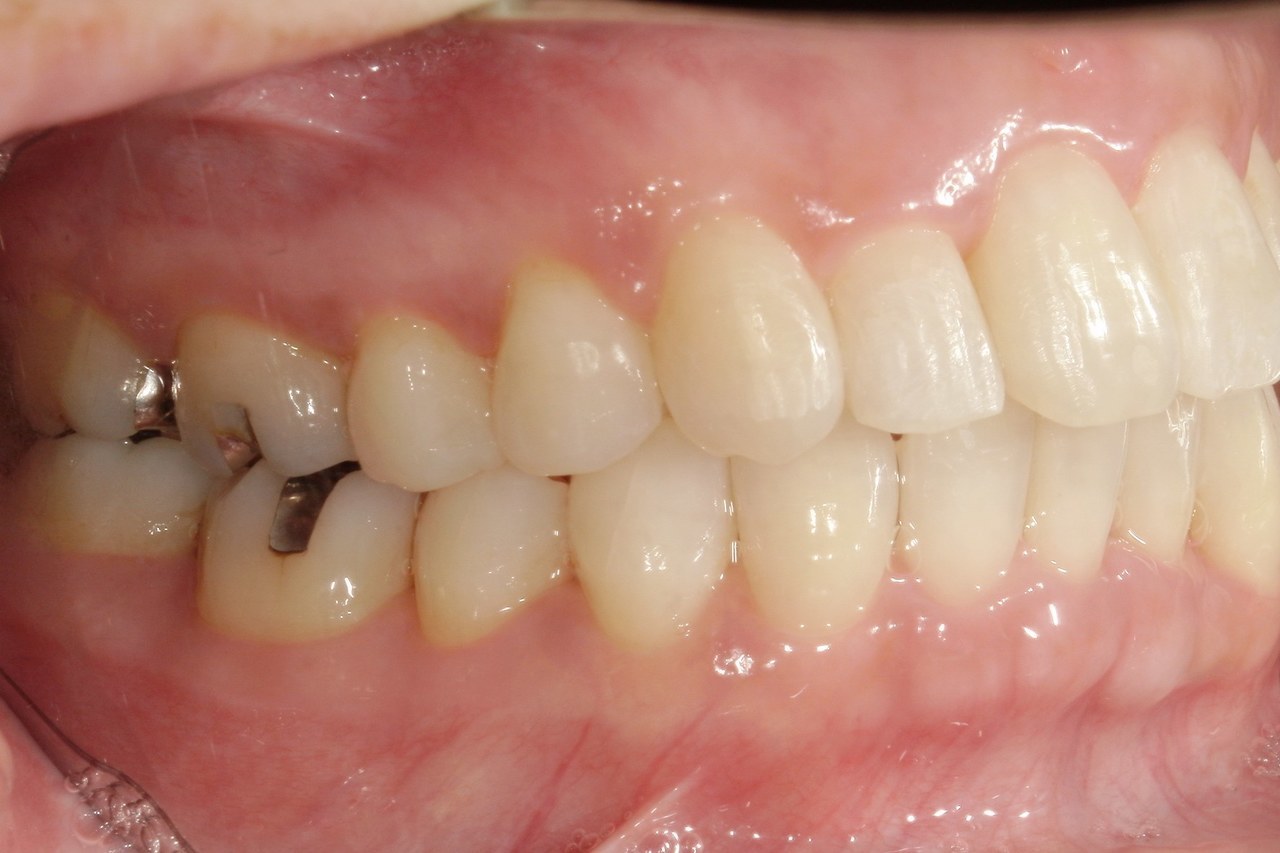

Before

浜松市中央区・自動車学校前駅のインビザラインの症例

After

M.I. 40代女性

上下の前歯をキレイに並べたい、中心がズレている、という主訴でご来院。上下前歯の叢生を治し、正中を合わせました。

治療の期間:R3. 4/13〜R5. 8/30

治療の価格:88万円